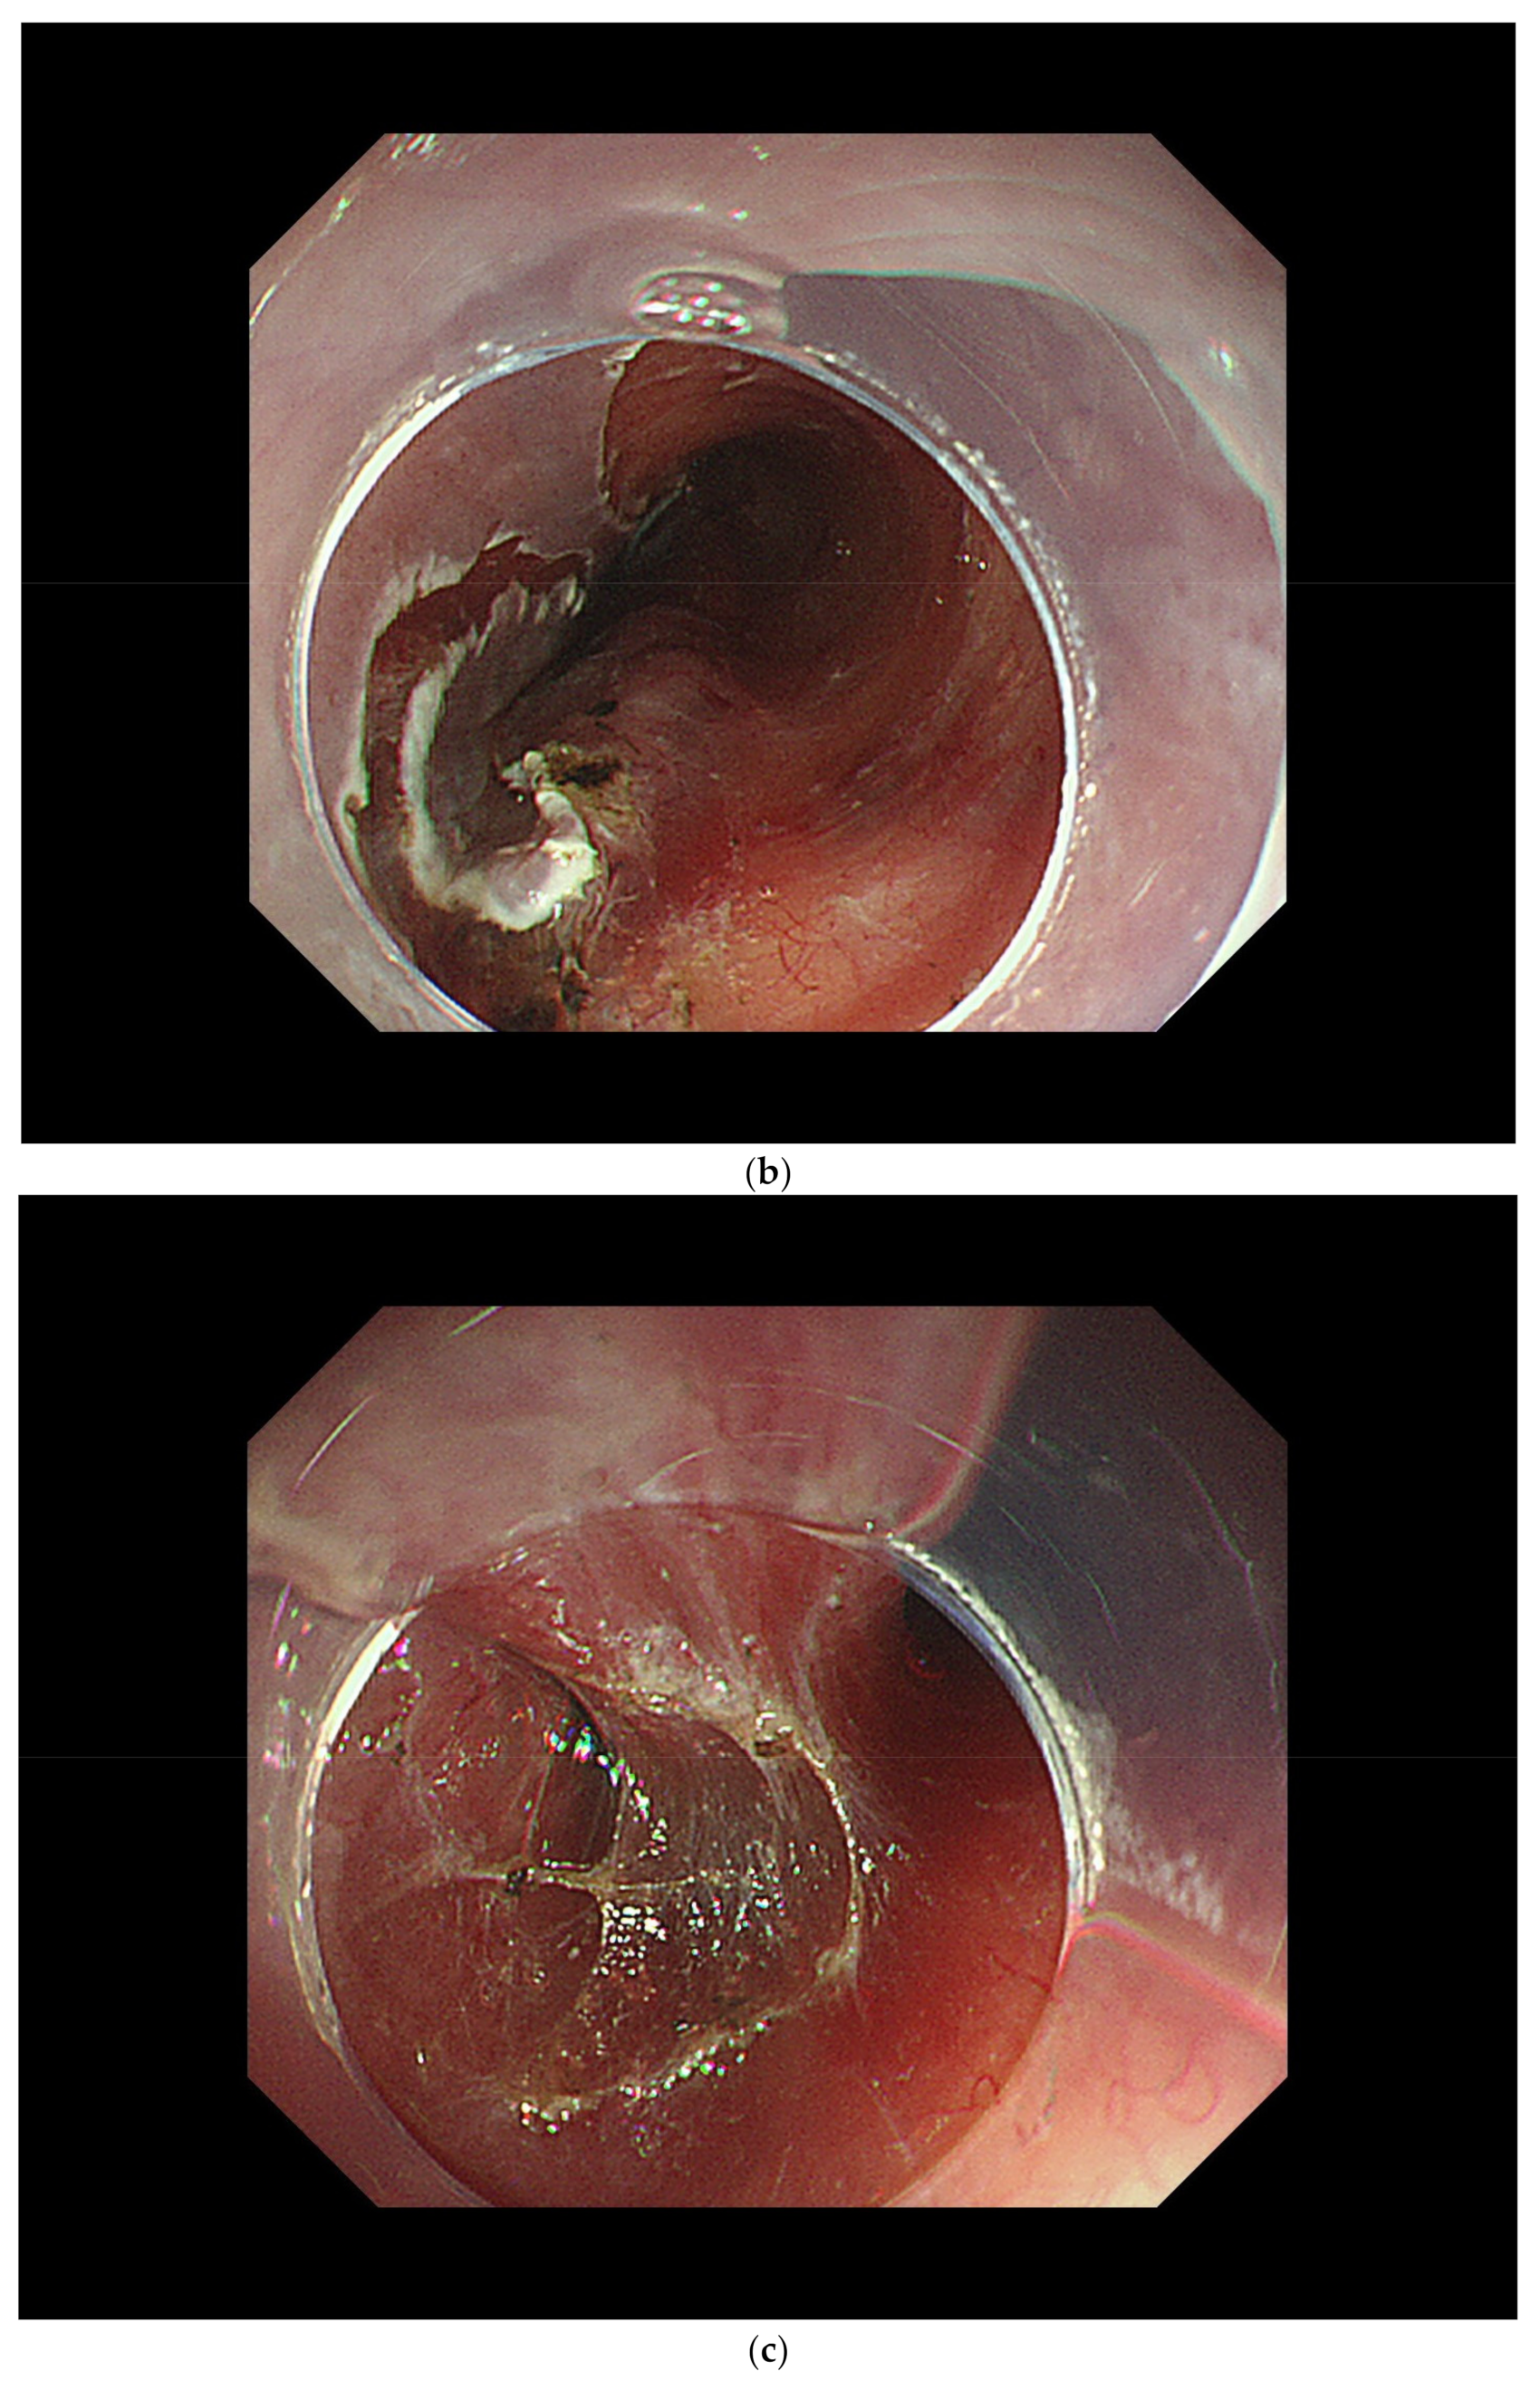

2.1. Modalities Used for Detection

2.2. Endoscopic Diagnosis of SCC

3.2. Diagnosis of Cancer Invasion Depth by White-Light Endoscopy and Magnifying Endoscopy

4.3. ER Procedure